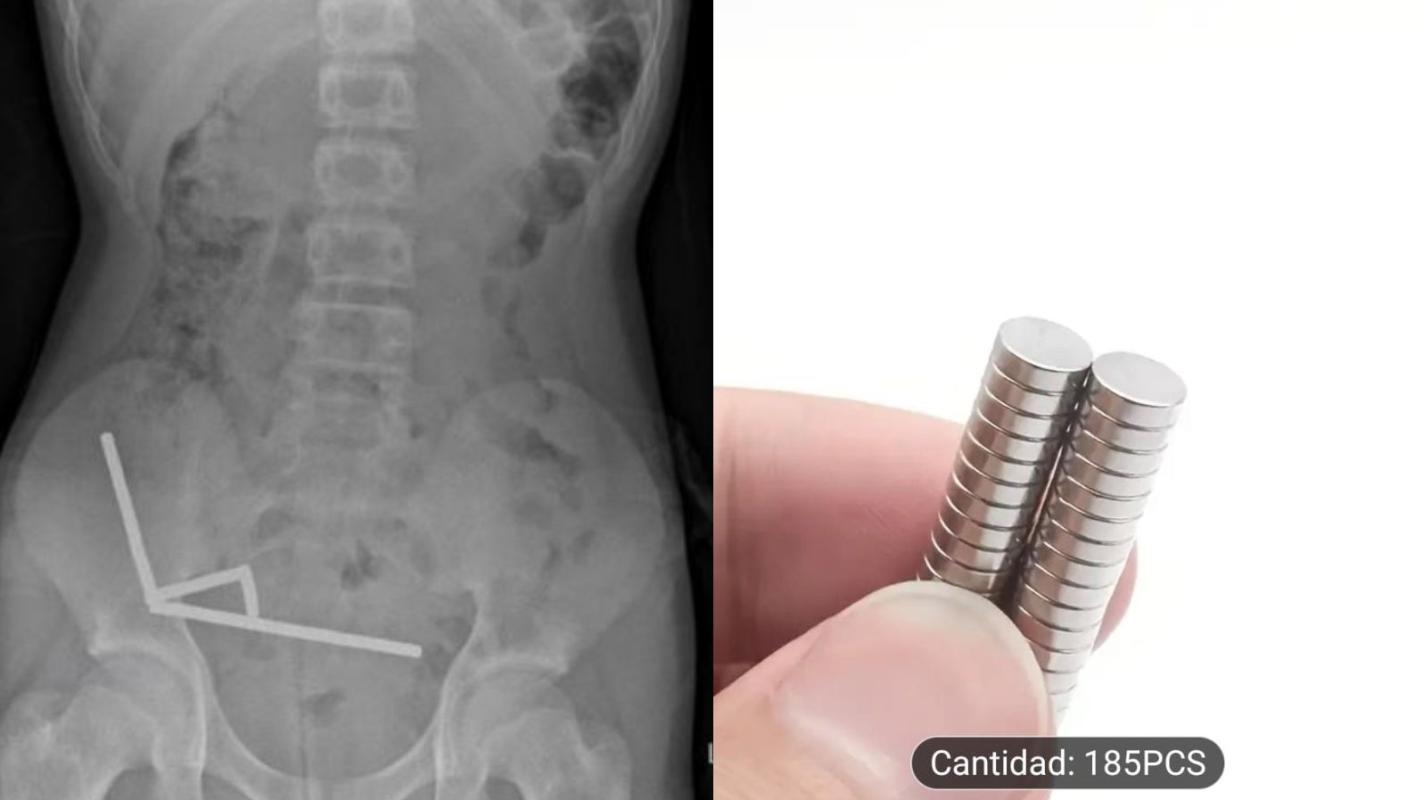

Radiografía del niño que tragó los imanes (NZ Medical Journal) - Temu

En la consulta, el niño de 13 años confesó que se había tragado entre 80 a 100 imanes de alta potencia (neodimio) de 5x2mm que había comprado por el comercio online Temu.

En el análisis físico, presentaba alta sensibilidad en el cuadrante inferior derecho de su abdomen, lo que fue confirmado por la radiografía abdominal, que reveló “cuatro cadenas lineales de imanes localizadas en el cuadrante inferior derecho del abdomen. Estas parecían ser partes separadas del intestino adheridas entre sí debido a las fuerzas magnéticas”.

En esta línea, en la publicación se detalla que los imanes estaban causando necrosis por presión en el ciego (la primera porción del intestino grueso) y dos áreas del intestino delgado. Por lo anterior, “se realizó una resección ileocólica y dos resecciones en cuña del intestino delgado para recuperar los imanes”.